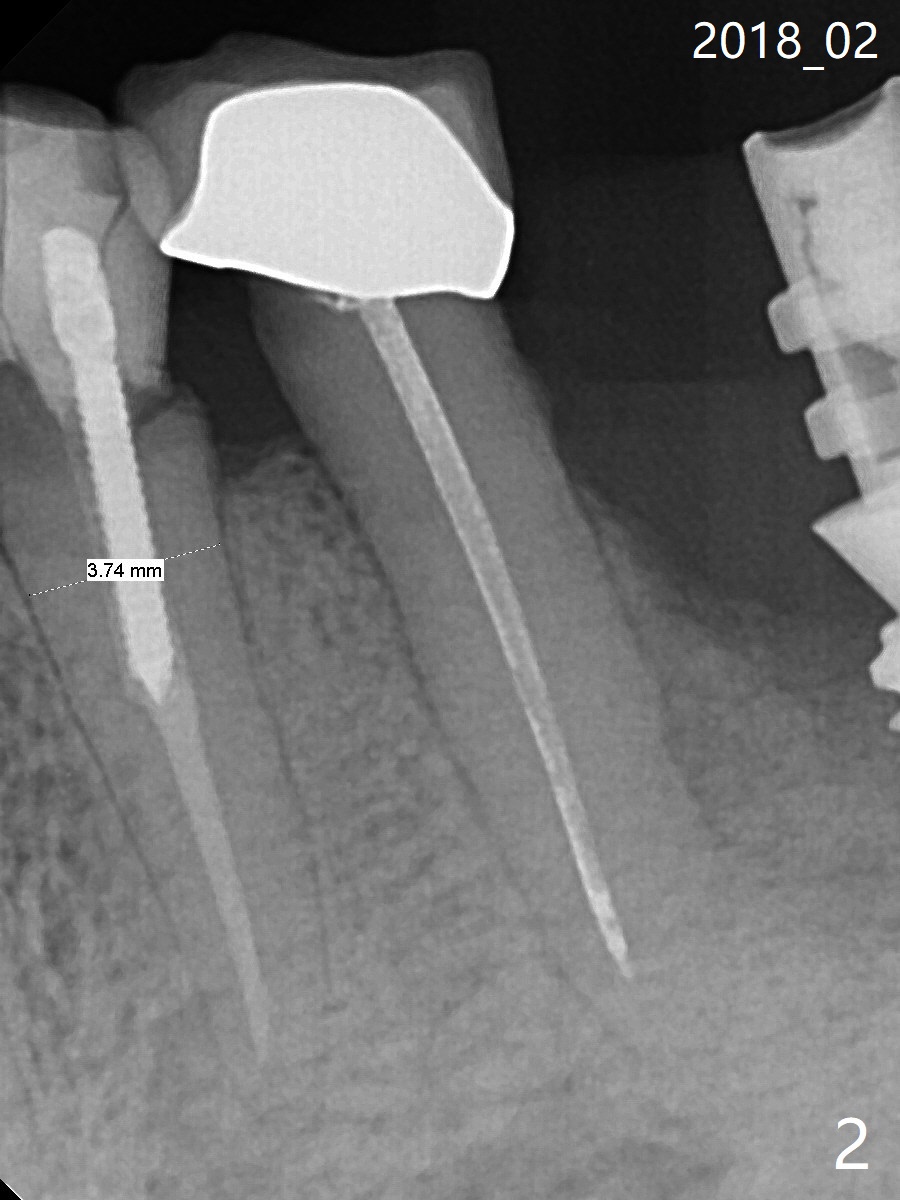

A 88-year-old man breaks the tooth #21 after RCT and post (Fig.1-3). Place a long SM implant for early final restoration, since he is a bruxer. The diameter of the implant will be 3.8-4.5 mm (Fig.2). Place the implant in the middle of the oval socket. Prepare endo ice for #23 before composite (Fig.3).